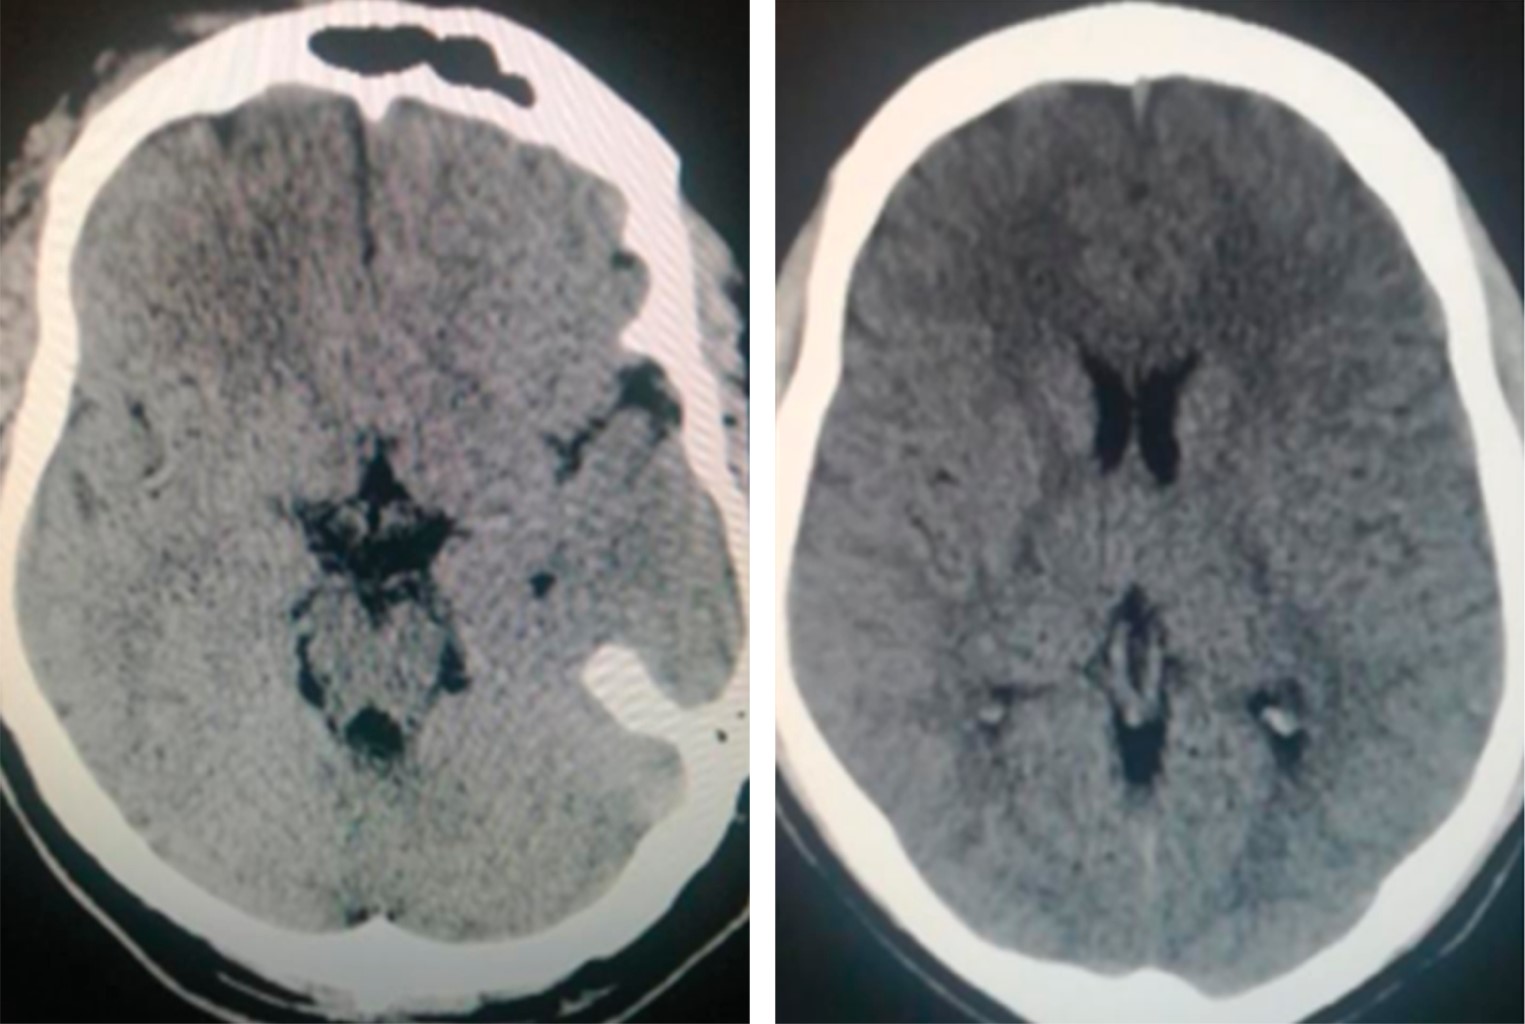

We present the clinical case of a 59-year-old patient with sepsis due to polymicrobial pneumonia with viral isolates conditioning bacterial infection and thrombosis. His chest scannography reported basals collapses with atelectasis and reticular interstitial infiltrates; Evolved with cognitive impairment related to multi-infarction vascular brain disease documented by single-photon emission brain tomography by nuclear medicine due to normal scannographies studies; Given the neurological evolution, extension studies were carried with transthoracic duplex Doppler echocardiogram which was normal, as well as a contrasted study of four neck vessels, electrical rhythm holter and complete metabolic profile also normal. We conducted a review in the literature with a view to providing understanding and evidence of the direct relationship between septic syndromes and viral infections with different states of hypercoagulability, inflammation and apoptosis.

Figure 2